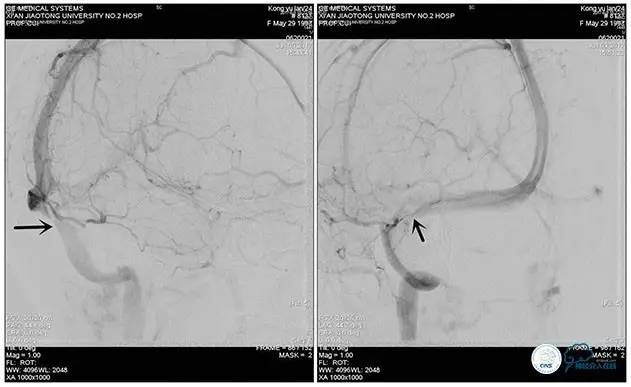

术后造影

术毕远近端压力差为:0